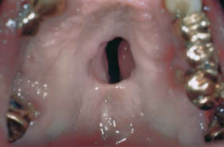

Tertiary syphilis: gumma

30% cases

Gumma causing a palatal fistula

Period of latency may last 1-30 years

Gumma may be an indurated and ulcerated lesion or may produce destruction (Granulomatous inflammation)